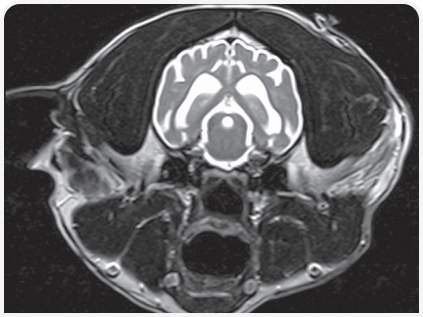

Диагноз ставится на основании изменения размера и формы черепа, неврологических признаков заболевания и нейровизуализации.

Практичным методом визуализации боковых желудочков является ультразвуковое исследование через открытый родничок.